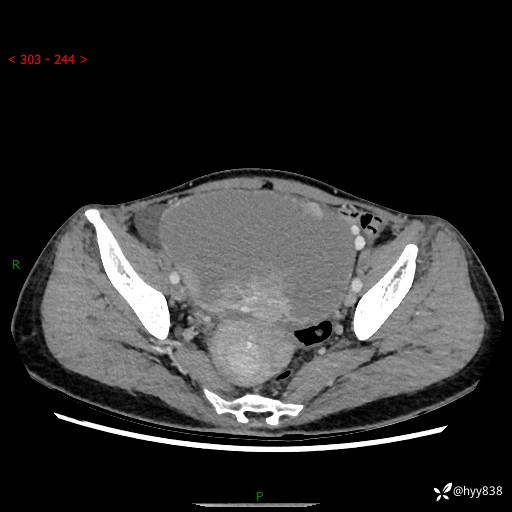

【患者信息】:女,50岁

【主诉】:外院超声发现腹盆肿块,为进一步诊治来我院,门诊已“盆腔肿块”收入院。

腹盆CT平扫+增强

【临床诊断】:盆腔肿瘤

【治疗经过及结果】:手术